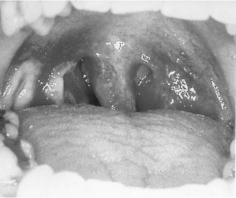

1.4.2.8.3三、临床表现